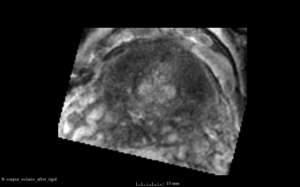

Fixed Volume as Reference

SimpleITK result after Initialization

SimpleITK result after rigid registration

BRAINSFit result after rigid without using masks and --useCenterOfGeometryAlign

• The rigid registration result is too much rotated and translated. Also the number of iteration steps varies with every computation. Reason might be that seed is set randomized and not set as done in BRAINSFit here. There is no option at the SimpleITK::ImageRegistrationMethod to set a metric seed.